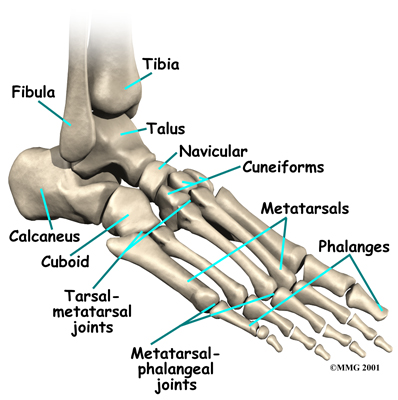

The skeleton of the foot centers around the talus, or ankle bone, which forms the main part of the ankle. The two bones of the lower leg, the large tibia and the smaller fibula, come together around the talus to form a very stable structure.

The two bones that make up the ‘hindfoot’ include the talus and the calcaneus, or heel bone. The talus is connected to the calcaneus at the subtalar joint. The ankle joint where the talus connects to the tibia and fibula allows the foot to bend up and down. The subtalar joint allows the foot to rock from side to side.

Just down the foot from the ankle is a set of five bones called tarsal bones that work together as a group. These bones are unique in the way they fit together. There are multiple joints between the tarsal bones. When the foot is twisted in one direction by the muscles of the foot and leg, these bones lock together and form a very rigid structure. When they are twisted in the opposite direction, they become unlocked and allow the foot to conform to whatever surface the foot is contacting.

The tarsal bones are connected to the five long bones of the foot called the metatarsals. The two groups of bones are fairly rigidly connected, without much movement at the joints.

The spring ligament complex is often involved in AAFD. This group of ligaments supports the talonavicular joint. The spring ligament complex works with the posterior tibial tendon and the plantar fascia to support and stabilize the longitudinal arch of the foot.

There are multiple factors contributing to the development of this problem. Injury to the nerves of the foot, laxity (looseness), or dysfunction of the spring ligament and tendon structures on the medial side of the foot, such as the posterior tibialis tendon, can all result in deformity of the foot and/or ankle resulting in AAFD. Subluxation (partial dislocation) of the subtalar or talonavicular joints can occur. A bone fracture is also a possible cause. The resulting joint deformity from any of these problems can lead to AAFD.